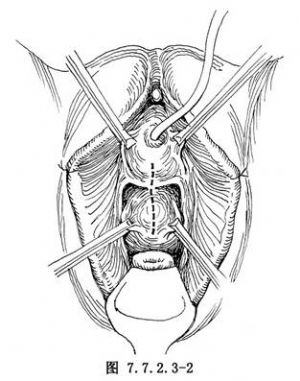

1.切口 小阴唇用细丝线固定于大阴唇上,重力拉钩牵开阴道。尿道置气囊导尿管,扩充气囊。做阴道前壁正中纵行切口,起自尿道口下方约1cm,向上延至膀胱颈部位,长约4cm(图7.7.2.3-2)。